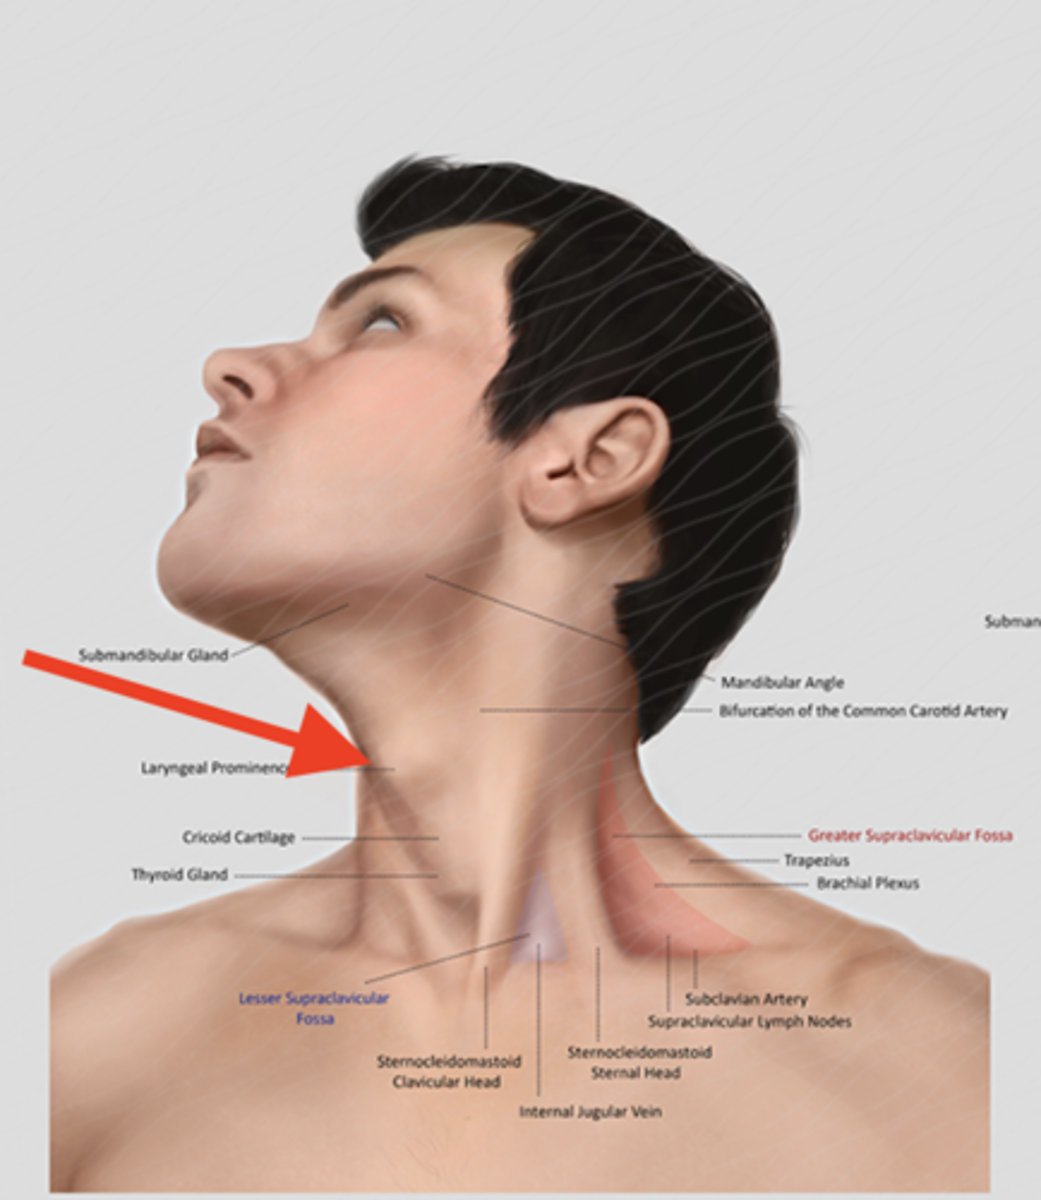

thyroid cartilage (surface anatomy)

Adam's apple